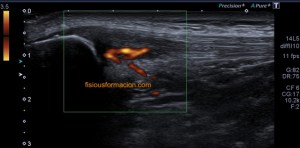

La radiografía revela aumento de las partes y se refrenda en la ecografía como puedes ver en la imagen aunque aún no hay afectación en el hueso en el caso que te presento hoy.

Ecografícamente y debido a su levedad, en el caso de hoy solo observamos cambios en las partes blandas de la cara lateral de la cabeza del quinto metatarsiano, este tejido se muestra heterogéneo, la cortical del hueso ligeramente prominente sin afectación de la misma.